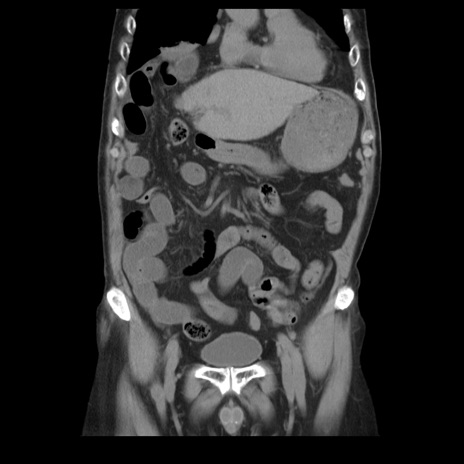

横断像

【症例】70歳代男性

【主訴】腹痛

【現病歴】肝硬変・肝細胞癌にてかかりつけの方。約9時間前に食後より腹痛出現。症状が徐々に増悪し、嘔吐出現したため来院。

【既往歴】肝硬変、肝細胞癌(RFA、TACE後)

【身体所見】意識清明、表情苦悶様、BT 36℃、BP 129/78mmHg、P 88bpm、SpO2 97%(RA)、右上腹部から心窩部にかけて圧痛あり、反跳痛なし、筋性防御あり。

【データ】WBC 5800、CRP 0.16